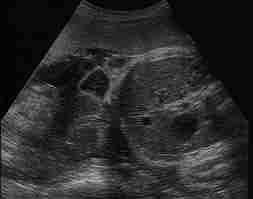

Abdominal Wall Defects

Major Disorders: Omphalocele, Gastroschisis

Diagnosis

Gastroschisis: Evisceration excluding the liver without a covering membrane,

Insertion of the umbilical cord onto the abdominal wallI

Giant Omphalocele: Evisceration including the liver with an intact covering

membrane, Insertion of the umbilical cord into the covering membrane